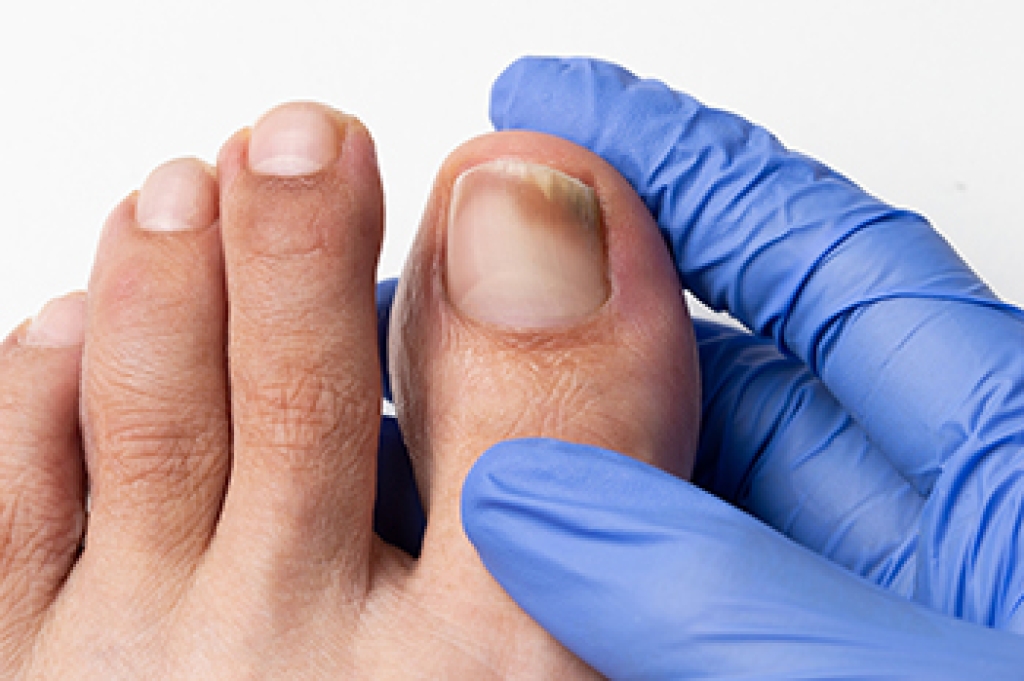

Swollen feet can also be caused by bone and tendon conditions, including fractures, arthritis, and tendinitis. Additionally, there may be skin and toenail conditions and an infection may cause the feet to swell. Patients who take medicine to treat high blood pressure may be prone to getting swollen feet.